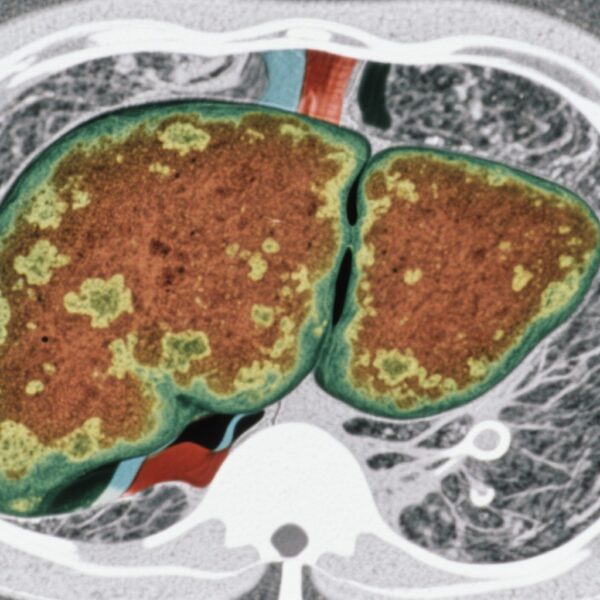

胆道癌(BTC)は、肝内・肝外胆管癌や胆のう癌を含む胆道上皮由来の多様な悪性腫瘍群です。他の消化器系がんに比べて発症頻度は低いものの、予後は不良であり、多くの患者が進行期で発見され、根治的な治療オプションが限られています。進行性BTCにおける中央値の全生存期間(OS)は、全身療法にもかかわらず依然として不吉であり、有効な治療法の開発が急務となっています。